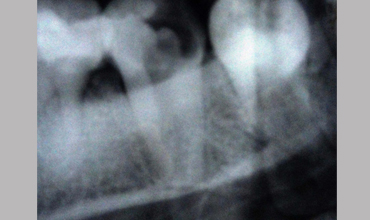

Management Of Single Root

Management Of Single Root With Single Canal In Mandibular Second Molar